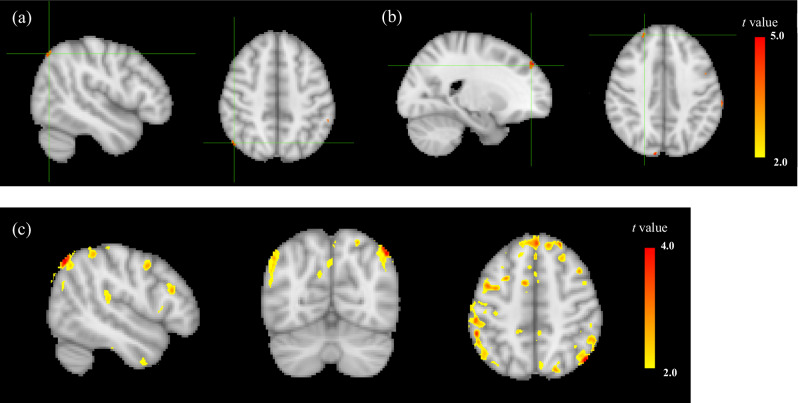

Impaired insight into illness occurs in up to 98% of patients with schizophrenia, depending on the stage of illness, and leads to negative clinical outcomes. Previous neuroimaging studies suggest that impaired insight in patients with schizophrenia may be related to structural and functional anomalies in frontoparietal brain regions. To date, limited studies have investigated the association between regional cerebral blood flow (CBF) and impaired insight in schizophrenia. Therefore, we sought to investigate the relationship between regional CBF, as measured by arterial spin labeling (ASL), and impaired insight in participants with schizophrenia. A total of 32 participants were included in the analysis. Impaired insight in patients with schizophrenia was measured using the VAGUS, Self-report (VAGUS-SR). Resting-state regional CBF was measured using pseudo-continuous ASL (pCASL) and extracted using SPM12 and REX toolbox. Whole brain analysis found that impaired insight was associated with higher regional CBF in the right angular gyrus, left supramarginal gyrus, and right superior frontal region when controlling for age, gender, smoking status, and illness severity. The results indicate that impaired insight in schizophrenia is related to regional CBF in frontoparietal areas. These neuroimaging findings can serve as therapeutic targets for intervention, such as with non-invasive brain stimulation.